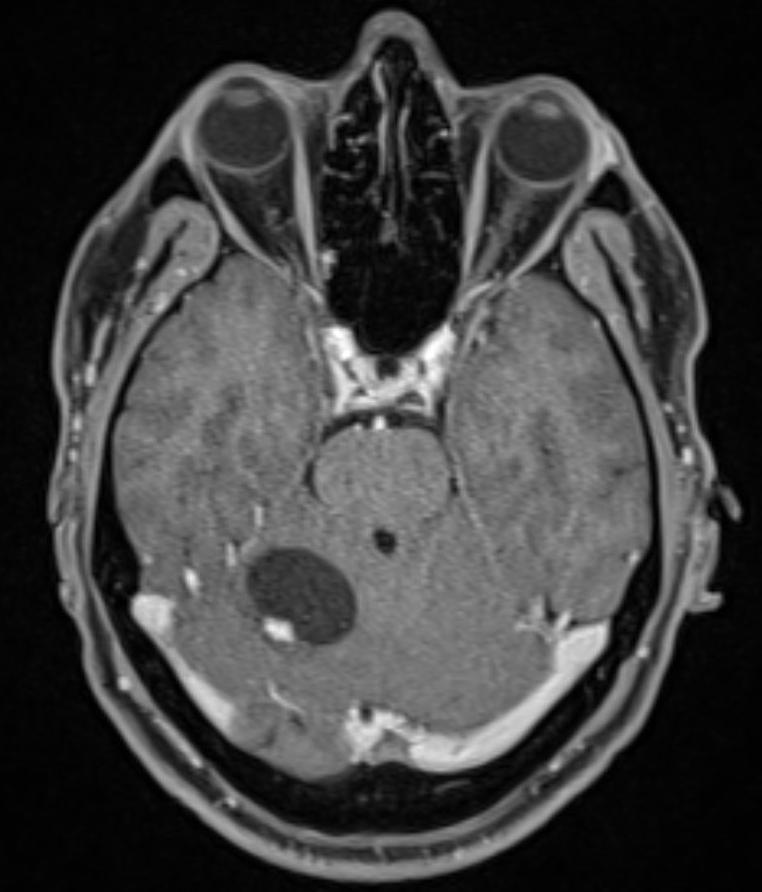

Bildgebung

Der Goldstandard in der Bildgebung von Hämangioblastomen ist die MRT Bildgebung. In einer digitalen Subtraktionsangiographie zeigt sich häufig ein stark vaskularisierter Nodulus mit Feedergefäßen, welcher suggestiv für ein Hämangioblastom ist.